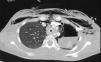

Presentamos el caso de una mujer de 15 años previamente sana que ingresa por fiebre, tos no productiva e insuficiencia respiratoria. Seis semanas antes había comenzado con un cuadro leve e intermitente de diarrea acuosa y en las 2 últimas semanas con fiebre y tos seca. En una consulta ambulatoria 10 días antes del ingreso la analítica mostraba: leucocitosis (15.660/mm3), anemia (Hb 11g/dL), ligera elevación de transaminasas (AST/ALT 62/75UI/L) y elevación significativa de PCR (243mg/dL). Se inició tratamiento con azitromicina y ambroxol, sin mejoría. Acudió en varias ocasiones a Urgencias por persistencia de la fiebre, la tos y disnea leve, destacando en la exploración la presencia de taquicardia sinusal, sibilancias e hipoxemia relativa, y en la radiografía de tórax, signos de hiperinsuflación. En su última visita a Urgencias presentaba mayor hipoxemia (SaO2 87%), la radiografía de tórax mostraba neumomediastino y enfisema subcutáneo (fig. 1), y la analítica: leucocitosis (23.590/mm3) con neutrofilia (78%), anemia (Hb 10g/dL), trombocitosis (643.000/mm3), elevación de PCR (180mg/dL) y procalcitonina (21ng/mL). Ingresó en planta de hospitalización con oxigenoterapia, bromuro de ipratropio y budesonida inhalados, metilprednisolona (20mg/12h) y levofloxacino. En pocas horas progresó a un cuadro de insuficiencia respiratoria muy grave que se hizo agónica, con ingurgitación yugular muy marcada, hipoxemia y acidemia respiratoria extremas (SaO2 37% con mascarilla de alta FiO2 y PaCO2 144mmHg con pH 6,9). Fue intubada sin dificultad, pero la ventilación mecánica resultó muy complicada como consecuencia de una extraordinaria resistencia en la vía aérea con hiperinsuflación, auto-PEEP e inestabilidad hemodinámica, que impedían alcanzar objetivos mínimos de oxigenación y ventilación a pesar de la utilización de volúmenes corrientes muy bajos, tiempos espiratorios prolongados y tratamiento vasopresor con noradrenalina a dosis muy elevada. En la auscultación llamaba la atención la presencia de una sibilancia inspiratoria muy aguda en la región esternal. En este contexto, presentó 2 episodios consecutivos de parada cardíaca de 10 y 5min con disociación electromecánica de los que se recuperó, en precario, con masaje cardíaco y adrenalina, continuando con hipoxemia, hipercapnia y acidemia muy graves (SatO2<50%, PaCO2 por encima del rango superior del gasómetro y pH 6,7), e inestabilidad hemodinámica extrema con necesidad de soporte vasopresor a dosis muy elevadas. Con la sospecha de obstrucción de la vía aérea central (OVAC) se decidió la realización de fibrobroncoscopia bajo asistencia circulatoria y respiratoria con membrana de oxigenación extracorpórea (ECMO). El procedimiento se llevó a cabo en quirófano bajo anestesia general mediante canulación abierta femoro-femoral y asistencia venoarterial. La fibrobroncoscopia mostró una obstrucción casi completa de la luz traqueal por un material blanquecino de aspecto mamelonado que se biopsió, obteniendo un material fibrino-leucocitario y mucoide sin atipias (fig. 2). Mediante cauterización con sonda de argón-plasma se consiguió una luz traqueal suficiente que facilitó la ventilación y una mejoría del intercambio gaseoso y hemodinámica que permitió, en el propio quirófano, la desconexión de la ECMO. Con la sospecha de un proceso inflamatorio se inició tratamiento con pulso de metilprednisolona (0,5g iv) y se continuó la antibioticoterapia. Unas 12h después, ya en una situación hemodinámica y respiratoria relativamente estables, se realizó una TAC toracoabdominal que mostró un engrosamiento concéntrico de la tráquea y los bronquios principales, neumomediastino, hidroneumotórax izquierdo, enfisema subcutáneo toraco-abdominal y neumorretroperitoneo (fig. 3). Se drenó el hidroneumotórax izquierdo y posteriormente se realizó una broncoscopia rígida en la que ya se apreciaba una clara reducción del material inflamatorio y de la ocupación traqueobronquial. Aun así, contemplando la posibilidad de recurrencia, se decidió la implantación de una prótesis traqueobronquial en «Y». La evolución posterior resultó favorable, con una recuperación neurológica y cardiorrespiratoria ad integrum que permitió la retirada precoz (∼24h) de la ventilación mecánica y finalmente el alta hospitalaria sin ningún tipo de secuela.